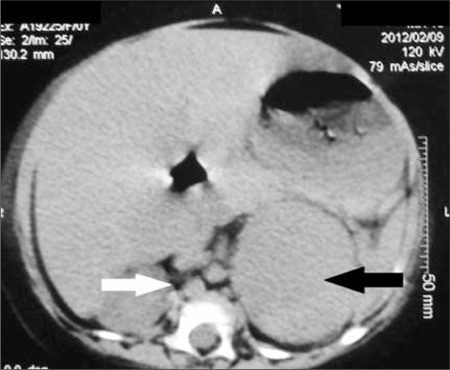

Radiology description

- Computed tomography (CT):

- Rounded, well delineated borders, homogeneous, clear separation from and no extension into surrounding structures, decreased attenuation compared to uninvolved adrenal parenchyma on non-contrast CT (≤10 HU), contrast enhancing (Theranostics 2012;2:516)

- Magnetic resonance imagining (MRI):

- Used to visualize microscopic fat (favoring ACA), "chemical shift" phenomenon (increased "in phase" signal intensity, decreased "out of phase" signal) (Theranostics 2012;2:516)

- 18FDG-PET:

- Malignant lesions have greater 18FDG uptake than liver (Theranostics 2012;2:516)

Radiology images